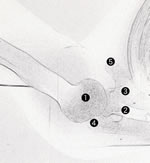

5・16・2 肘関節側面撮影

5・16・2 肘関節側面像